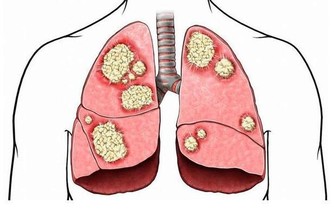

對於人體來說,這部分營養無法被消化,也無法被利用,但這並不意味著它們沒用。這時身體內的不法分子,如潛在的腫瘤因子等就會接收這些“廢物”,供自己享用,一旦時機成熟就會變成令人談之色變的腫瘤。